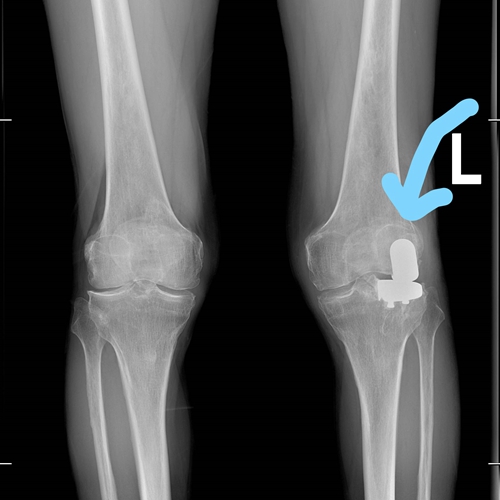

很快团队制定了手术方案,经患者和家属同意,左膝关节外侧单髁置换手术如期开展。术后,张老伯恢复非常好,第二天就下地行走了,他逢人就说这个手术做的效果好!

李云飞主任介绍,单髁置换是一种精准的部分关节置换术,针对膝关节中仅单侧间室发生严重磨损的病变。与需要置换全部关节面的全膝关节置换相比,单髁置换具有显著优势:首先,其手术创伤较小,患者术后疼痛更轻、出血更少,因此恢复更快。其次,它能更大程度地保留膝关节自然的韧带结构,特别是交叉韧带,这对于维持关节的稳定性、舒适度及正常的生理活动轨迹至关重要。此外,李主任指出,该技术不仅适用于张老伯这样的外侧磨损病例,对于局限于内侧间室的关节病也同样适用,均可获得良好的治疗效果。